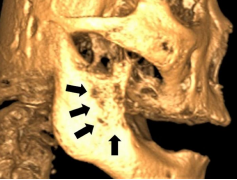

The patient was documented to be a known case of end-stage prostate cancer. He was initially diagnosed with adenocarcinoma of the prostate gland in June 2014 via pathology examination of specimens of his trans-urethral resection of his prostate (TURP) gland. The Gleason score of his prostate cancer was 4+5 = 9, and his serum prostate-specific antigen (PSA) was high (65 ng/mL). he had an isotope bone scan in July 2014 which had demonstrated multiple bone metastases involving his left 4th rib, 4th lumbar spine, sacrum, and left pubic bone but which had not involved his mandible. He was treated with androgen deprivation therapy (Lucrin) until December 2015, and his treatment was followed by seven months of antineoplastic agents (Abiraterone acetate) from December 2016 to July 2017 due to his persistent high baseline of serum PSA value >100 ng/mL. His prostate cancer disease had progressed and the patient was treated with non-steroidal antiandrogen (Enzalutamide) from July 2017. His serum PSA value did not respond to the treatment he had. By October 2017, his serum PSA level was 120 ng/mL, which had coincided with his first clinical symptom of numb chin syndrome. He underwent a cone-beam computed tomography (CBCT) scan which had demonstrated erosion of bone within the anterior part of his ascending ramus and retromolar region (see Figure 2). An incisional biopsy of the lesion was then undertaken for pathology examination.

Figure 2: CBCT image showing erosion of bone at the anterior part of right ramus of mandible and retromolar region. Reproduced from: [12] Under the Creative Commons Attribution License.